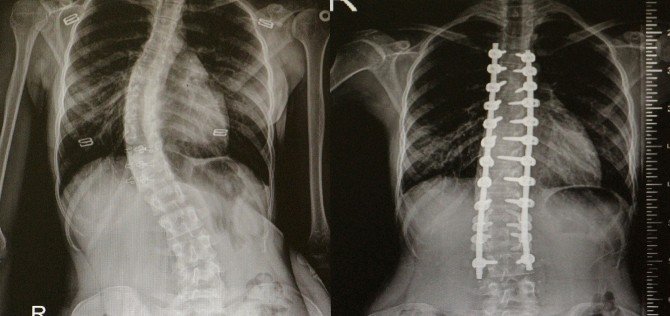

Omurga Eğriliği Olanlar Omü’de Şifa Buluyor

Skolyoz(omurga eğriliği) olan hastalar Ondokuz Mayıs Üniversitesi(OMÜ) Tıp Fakültesi'nde şifa buluyor.

Skolyozun genellikle çocuklarda görülen bir hastalık olduğunu ifade eden OMÜ Tıp Fakültesi Ortopedi ve Travmatoloji Anabilim Dalı Öğretim Üyesi Yrd. Doç. Dr. Mesut Kılıç, omurga eğriliği olan hastaların OMÜ Tıp Fakültesi'nde rahatlıkla tedavi edildiğini söyledi. Skolyoz cerrahisinde modern tekniklerin kullanıldığını belirten Kılıç, nöromonitörizasyon uygulamasıyla felç riskini yüzde sıfıra kadar indirdiklerini söyledi.

Skolyozun özellikle kız çocuklarda daha sık görülen bir durum olduğunu söyleyen Yrd. Doç. Dr. Mesut Kılıç, "Skolyoz hastalığı özellikle çocuklarda ve gençlerde gerek kozmetik gerekse fonksiyonel açıdan şikayetlere sebep oluyor. Tedavide çoğunlukla cerrahi dışı yöntemler uygulanır. Korse, egzersiz gibi. Fakat bazı hastalarda cerrahi tedavi gerektirmektedir. Cerrahide günümüzde modern teknikler kullanılmaktadır. Halk arasında platin diye bilinen uygulamalarla düzeltme sağlanmaktadır. Ayrıca son dönemlerde teknolojik gelişmelerle ortaya çıkan nöromonitörizasyon dediğimiz bir sistem uygulanıyor. Hasta uyutularak bilgisayara bağlanıyor. Ameliyat sırasında bir felç durumu var mı yok mu? Sinir yapılarında bir zedelenme var mı yok mu bunu bize bildiriyor. Halk arasında bu tür ameliyatlarda "felç olursunuz" korkusunu biz çok duyuyoruz. Fakat bu uygulama ile felç riskini yüzde sıfıra yakın indiriyoruz" dedi.